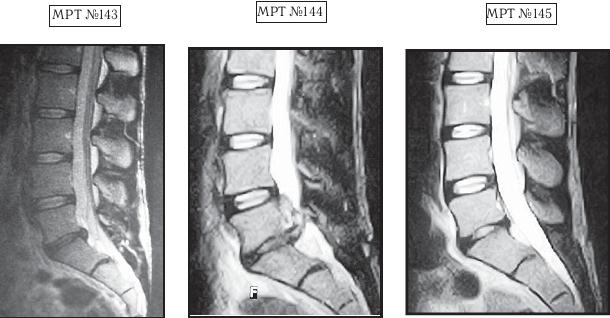

На МРТ № 139 — состояние поясничного отдела позвоночника: рецидив грыжи межпозвонкового диска после хирургической операции. Наблюдается абсолютный стеноз спинномозгового канала, грыжа межпозвонкового диска в сегменте LV-SI , осложнённая массивным секвестром с его миграцией как в каудальном (вниз), так и в краниальном (вверх) направлении. Размер грыжи дорсально — до 14,5 мм, каудально-краниально — до 26,8 мм. На МРТ № 140 наблюдается состояние поясничного отдела позвоночника после лечения методом вертеброревитологии: отсутствие грыжи межпозвонкового диска в сегменте LV-SI , отсутствие стеноза позвоночного канала. А вот этот случай запомнился упорством пациента, страх которого перед операцией был столь велик, несмотря на значительные боли, что по сути сами нейрохирурги, уставшие объяснять ему очевидные вещи и знавшие не понаслышке о методе вертеброревитологии, «переадресовали» строптивого пациента ко мне в клинику. Но, как говорится, всё, что ни делается, — всё к лучшему. ![]() На МРТ № 141 наблюдается состояние поясничного отдела позвоночника: секвестрированная грыжа межпозвонкового диска в сегменте LV-SI, абсолютный стеноз спинномозгового канала. На МРТ №°142 — состояние поясничного отдела позвоночника данного пациента после лечения методом вертеброревитологии: отсутствует грыжа межпозвонкового диска в сегменте LV-SI, более того, наблюдается активизация репаративного процесса в межпозвонковом диске данного сегмента. Состояние данного пациента было тяжёлым, в течение двух месяцев боли не купировались и он практически не спал. Нейрохирурги настаивали на срочной операции и были правы: показания к операции в данном случае — 100 %. Но пациент испытывал сильное беспокойство и страх по этому поводу, так как после аналогичной операции его родственник утратил способность к самостоятельному передвижению, стал инвалидом и потерял доходную работу. Ну что поделаешь, если человек был свидетелем таких печальных последствий, как говорится в пословице, — только слепой не боится призраков. Как врачи ни объясняли сложность его ситуации, пациент упорно не хотел оперироваться, а лекарства уже практически не действовали. Но нейрохирурги ведь тоже люди, терпение у них хоть и большое, но не «железное». В результате они дали пациенту адрес клиники вертеброревитологии. Как оказалось впоследствии, эта попытка нейрохирургов помочь пациенту была поистине их «соломоновым решением». Бывали случаи, когда пациенты с большими секвестрированными грыжами проходили всего лишь один курс лечения (24 сеанса), после которого наблюдалось не только устранение грыж, но и происходило довольно быстрое восстановление как межпозвонковых дисков, так и биомеханики позвоночника. Какие обстоятельства этому способствовали? Помимо построения биомеханической конструкции методом вертеброревитологии, этому также способствовали индивидуальные особенности данных пациентов (приемлемые для регенерации возрастные характеристики пациента (до 60 лет), отсутствие лишнего веса, наличие хорошего иммунитета и много других предрасполагающих к данному лечению факторов), соблюдение пациентами элементарных условий для реабилитации (восстановления) позвоночника. Такие случаи, где было достаточно одного курса методом вертеброревитологии, конечно, единичны. Однако они весьма показательны по вариабельности возможностей мобилизации и восстановления человеческого организма. Вот один из таких случаев. Он связан с моим пациентом — известным певцом, телеведущим да и просто хорошим человеком. Как в этом случае, так и в дальнейшем по этическим соображениям я не буду называть фамилии данных людей, а буду опираться лишь на конкретные результаты.